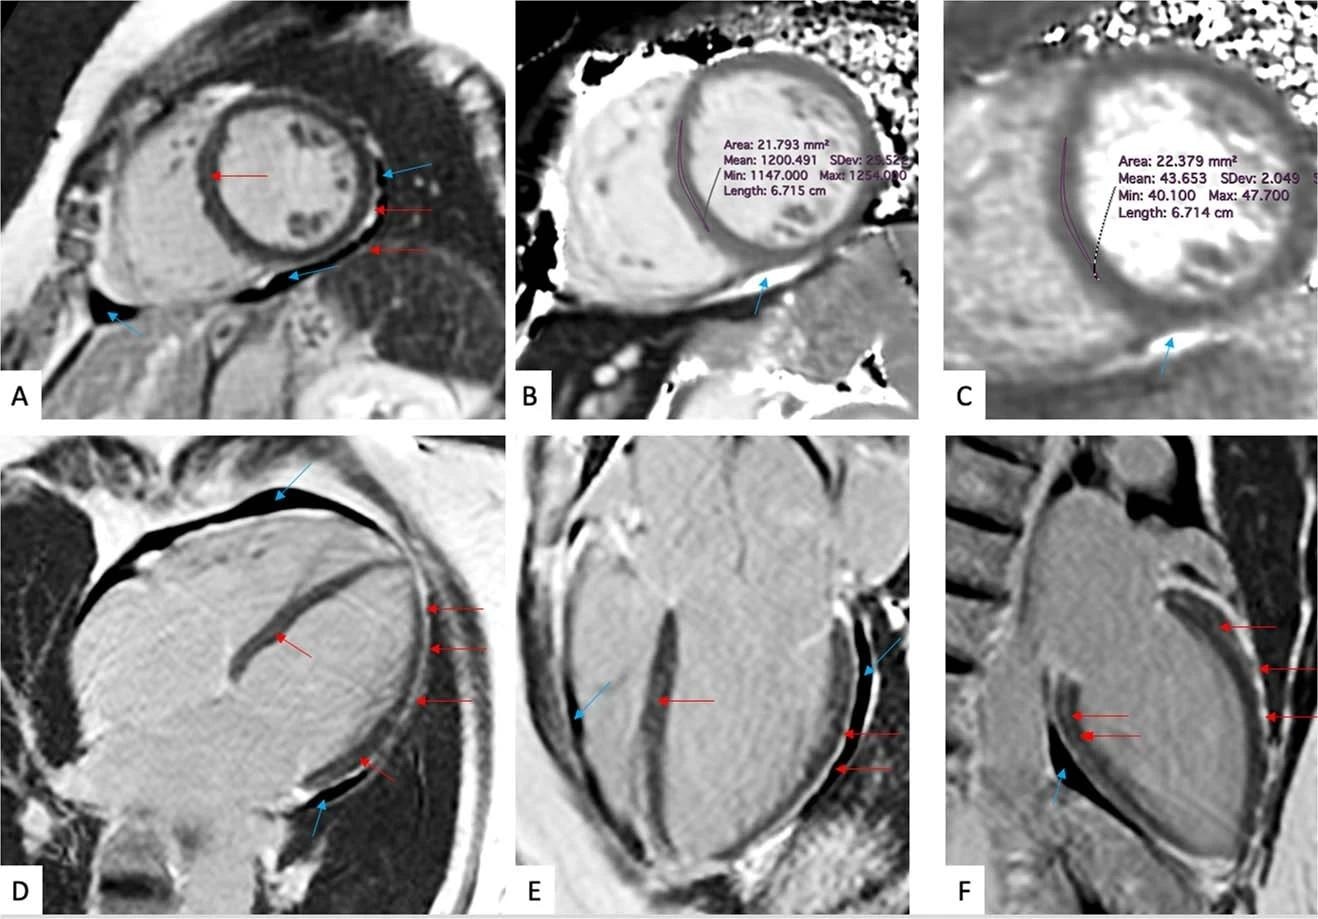

(a-f) Late gadolinium enhancement imaging (A, D-F) and Native T1 (B) and T2 (C) mapping measurements of a 57-year-old woman evaluated 201 days after COVID-19 infection. This individual reported dyspnea, palpitations, and chest pain, worsening on minimal exertion. Late gadolinium enhancement imaging allows to visualize regional accumulation of the gadolinium-based contrast agent along the outer rim of the myocardial free wall (red arrows), as well as within the thickened pericardial layers, separated by small amounts of pericardial effusion (blue arrows).

CMR imaging techniques can detect diffused inflammatory myocardial involvement (a non-specific measure of abnormal myocardium) by T1 mapping and myocardial water content by T2 mapping. The late gadolinium enhancement (LGE) denoted regional myocardial injury. On the other hand, the accumulation of gadolinium contrast agents helped visualize thickened pericardial layers.